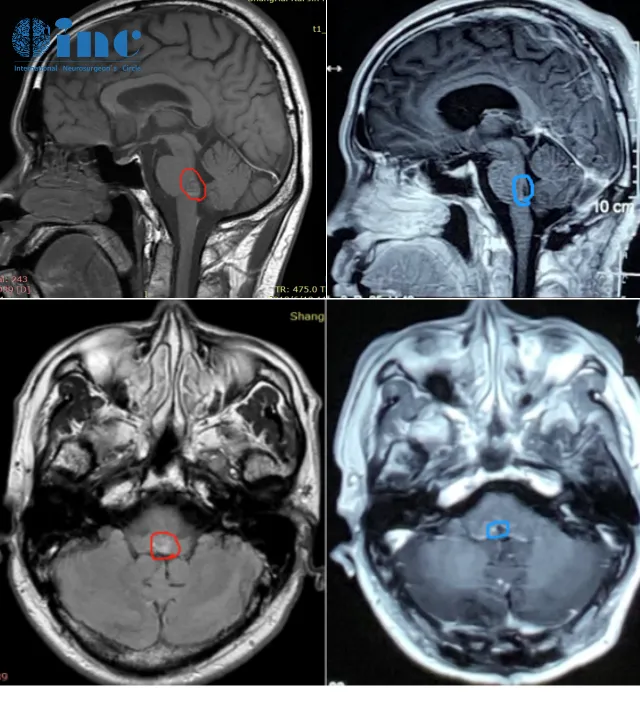

张先生,脑干海绵状血管瘤

2019年5月,第二次出血,张先生再次出现失明症状。CT显示症状较轻,但医生仍建议保守(手术或致不可逆神经损伤)。他做好“与病共存”准备,结合首次保守恢复经验,选择居家休养。

随访时,为他手术的巴教授查看片子后表示“手术很成功”,并鼓励他“做力所能及的事没问题”。他说:“我对现在的状况很满意,这是我自己选择的人生——从‘交代后事’到‘正常生活’,我已经很幸运了。”